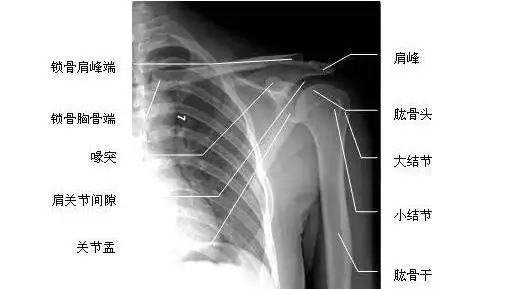

肩关节穿胸位片图片

肩关节正位-x线片

图片尺寸512x289

ap in internal rotation肩胛骨内旋正位六ap view 肩关节正位(胸片位